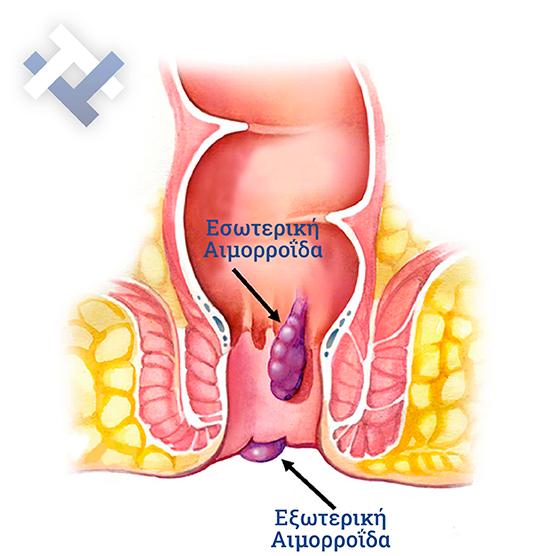

- Xωρίς Χειρουργείο με ελαστικούς δακτυλίους (Τεχνική BARON-RBL)

- Xωρίς Χειρουργείο με ελαστικούς δακτυλίους (Τεχνική BARON-RBL)

Ο Γενικός Χειρουργός Λιάγκος Γεώργιος MD PhD εκτελεί τις επεμβάσεις Λαπαροσκοπικά, Ενδοσκοπικά, Ανοιχτά Ελάχιστα Επεμβατικά και με Laser. Η θεραπεία εξατομικεύεται σε κάθε ασθενή ανάλογα με τις ανάγκες του. Αναλαμβάνει περιπτώσεις όπως κήλες και κοιλιοκήλες (αντιμετώπιση βουβωνοκήλης, αντιμετώπιση ομφαλοκήλης, θεραπεία επιγαστρικής κήλης, κήλη των αθλητών (Σύνδρομο κοιλιακών προσαγωγών), αντιμετώπιση μετεγχειρητικής κήλης, θεραπεία Μηροκήλης), πέτρες στη χοληδόχο κύστη, λαπαροσκοπική χολοκυστεκτομή, αντιμετώπιση Κύστη Κόκκυγος με λέιζερ (laser), παθήσεις πρωκτού, χειρουργική laser σύγχρονων κυκλικών ινών (αιμορροΐδες αντιμετώπιση, θεραπεία αιμορροϊδων με laser (LHP), αφαίρεση αιμορροΐδων με υπερήχους (HALL-RAR), χωρίς Χειρουργείο με ελαστικούς δακτυλίους (Τεχνική BARON-RBL), θεραπεία ραγάδας πρωκτού (Ραγάδα δακτυλίου), θεραπεία περιεδρικού συριγγίου, θεραπεία περιεδρικού αποστήματος, κονδυλώματα πρωκτού Θεραπεία, δερματικό ράκος (Skin tag) εκτομή, αντιμετώπιση Kνησμού, καρκίνος πρωκτού θεραπεία), παθήσεις Δέρματος, χειρουργική με laser CO2, αφαίρεση μορφωμάτων δέρματος - βιοψίες, αφαίρεση ελιάς (Σπίλου), σμηγματογόνος κύστης θεραπεία, αφαίρεση λιπώματος, είσφρυση όνυχος χειρουργείο, καρκίνος δέρματος θεραπεία, οξεία σκωληκοειδίτιδα, παθήσεις Λεπτού και Παχέος Εντέρου, ειλεός λεπτού εντέρου, εκκολπωμάτωση (Εκκολπωματίτιδα) σιγμοειδούς, καρκίνος παχέος εντέου, κολοστομίες, port χημειοθεραπείας κ.α.

Ο Γενικός Χειρουργός Λιάγκος Γεώργιος MD PhD εκτελεί τις επεμβάσεις Λαπαροσκοπικά, Ενδοσκοπικά, Ανοιχτά Ελάχιστα Επεμβατικά και με Laser. Η θεραπεία εξατομικεύεται σε κάθε ασθενή ανάλογα με τις ανάγκες του. Αναλαμβάνει περιπτώσεις όπως κήλες και κοιλιοκήλες (αντιμετώπιση βουβωνοκήλης, αντιμετώπιση ομφαλοκήλης, θεραπεία επιγαστρικής κήλης, κήλη των αθλητών (Σύνδρομο κοιλιακών προσαγωγών), αντιμετώπιση μετεγχειρητικής κήλης, θεραπεία Μηροκήλης), πέτρες στη χοληδόχο κύστη, λαπαροσκοπική χολοκυστεκτομή, αντιμετώπιση Κύστη Κόκκυγος με λέιζερ (laser), παθήσεις πρωκτού, χειρουργική laser σύγχρονων κυκλικών ινών (αιμορροΐδες αντιμετώπιση, θεραπεία αιμορροϊδων με laser (LHP), αφαίρεση αιμορροΐδων με υπερήχους (HALL-RAR), χωρίς Χειρουργείο με ελαστικούς δακτυλίους (Τεχνική BARON-RBL), θεραπεία ραγάδας πρωκτού (Ραγάδα δακτυλίου), θεραπεία περιεδρικού συριγγίου, θεραπεία περιεδρικού αποστήματος, κονδυλώματα πρωκτού Θεραπεία, δερματικό ράκος (Skin tag) εκτομή, αντιμετώπιση Kνησμού, καρκίνος πρωκτού θεραπεία), παθήσεις Δέρματος, χειρουργική με laser CO2, αφαίρεση μορφωμάτων δέρματος - βιοψίες, αφαίρεση ελιάς (Σπίλου), σμηγματογόνος κύστης θεραπεία, αφαίρεση λιπώματος, είσφρυση όνυχος χειρουργείο, καρκίνος δέρματος θεραπεία, οξεία σκωληκοειδίτιδα, παθήσεις Λεπτού και Παχέος Εντέρου, ειλεός λεπτού εντέρου, εκκολπωμάτωση (Εκκολπωματίτιδα) σιγμοειδούς, καρκίνος παχέος εντέου, κολοστομίες, port χημειοθεραπείας κ.α.